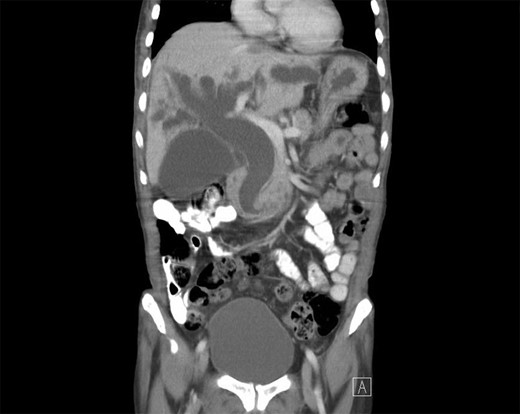

The patient is a 63-year-old Chinese male who presented with lethargy, 10-pound weight loss and painless jaundice for 1 week. Patient had a prior episode of jaundice of unclear etiology 2 years prior treated medically and had just emigrated from China 1 month prior to admission. Patient was febrile to 102.4°F, jaundiced with a total bilirubin of 18.5 mg/dL. Abdominal ultrasound showed intra and extrahepatic bile duct dilation, the distal CBD was dilated to 25 mm. Patient underwent endoscopic retrograde cholangiopancreatography (ERCP), which showed thick yellow mucus and no stones (Fig. 1). A sphincterotomy was performed and a pigtail stent placed. Computed tomography (CT), magnetic resonance imaging and magnetic resonance cholangiopancreaticogram failed to show a pancreatic head mass, distal CBD mass or stones causing obstruction (Fig. 2). Cold forceps biopsy of the papilla, endoscopic ultrasound with fine needle aspiration biopsy (FNAB) of pancreatic head, and CBD brushings were all nondiagnostic. CBD stents occluded two times in 2 weeks’ time secondary to thick mucus, requiring multiple ERCPs with stent exchanges (Fig. 3). After extensive multidisciplinary discussions regarding unclear etiology of distal CBD obstruction and extensive discussion with patient and family, the decision was made to perform a Whipple procedure for diagnosis and definitive treatment. Intraoperatively, choledochoscopy was performed, which showed very thick yellow mucus and frond-like mucosa near the ampulla. Final pathology showed a 2.0 × 1.5 × 0.5 cm3 granular lesion in the distal CBD. There was prominent biliary epithelial proliferation with tubular–papillary architecture and minimal nuclear atypia in association with chronic inflammation, stroma reaction and smooth muscle proliferation. The overall histological change in the distal CBD resembled that of AH seen in gallbladder, likely non-neoplastic change (Figs 4 and 5). At 1 year follow-up, he is doing well and his jaundice has resolved.

CT of the abdomen and pelvis showing severely dilated intra and extrahepatic bile ducts.